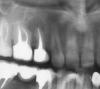

sas01 Опубликовано 23 декабря, 2009 Поделиться Опубликовано 23 декабря, 2009 Всем добрый день!Посоветуйте, нужно ли/возможно ли сохранить этот (верхнюю 5-ку) зуб. Был на консультации в 2-х клиниках, в одной берутся делать РВК, но без гарантии и по стоимости эта процедура может быть соизмерима с имплантацией, во второй – однозначно удаление. Киста обнаружена в 2005 году, проводилось лечение через канал, после чего на зуб была установлена вкладка + коронка. В данный момент началось обострение, на десне появился отек, хотя зуб не болит. Курс антибиотиков результата не дал. Нужен компетентный совет – бороться или терять (жалко, уж больно много сил было вложено в этот зуб), или РВК в данном случае только оттяжка времени и сил? Ссылка на комментарий